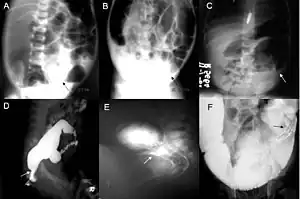

Definitive diagnosis is made by suction biopsy of the distally narrowed segment.[26] A histologic examination of the tissue would show a lack of ganglionic nerve cells. Diagnostic techniques involve anorectal manometry,[27] barium enema, and rectal biopsy. The suction rectal biopsy is considered the current international gold standard in the diagnosis of Hirschsprung's disease.[28]

Radiologic findings may also assist with diagnosis.[29] Cineanography (fluoroscopy of contrast medium passing anorectal region) assists in determining the level of the affected intestines.

Hirschsprung’s disease is a congenital disorder of the colon in which certain nerve cells, known as ganglion cells, are absent, causing chronic constipation.[41] The lack of ganglion cells is in the myenteric plexus (Auerbach's plexus), which is responsible for moving food in the intestine. A barium enema is the mainstay of diagnosis of Hirschsprung’s, though a rectal biopsy showing the lack of ganglion cells is the only certain method of diagnosis.